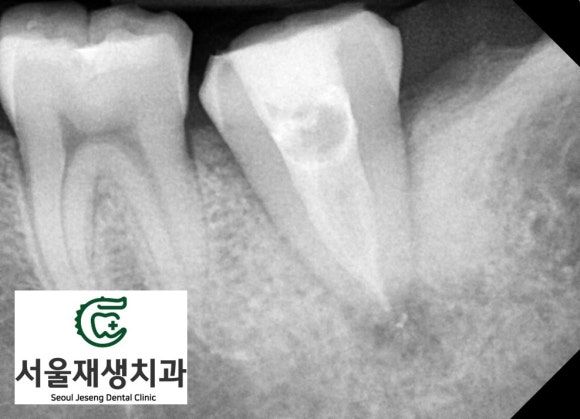

파노라마 엑스레이를

찍어보았습니다.

왼쪽 아래 어금니에

(사진 상 오른쪽입니다.)

신경치료를 받은 흔적과 동시에

뿌리 끝에 매달려 있는

염증 주머니가 관찰됩니다.

추가 촬영을 통해

해당 치아의 상태를

보다 면밀히 파악할 수 있습니다.

치아 내부의 잔존 조직들이

시간이 지남에 따라 부패하여

뿌리 끝에 나있는 작은 구멍

(=치근단공)을 향해

염증 물질을 내뿜습니다.

그 결과,

뿌리 끝을 중심으로 하는

동그란 염증주머니가

생기는 것이죠.